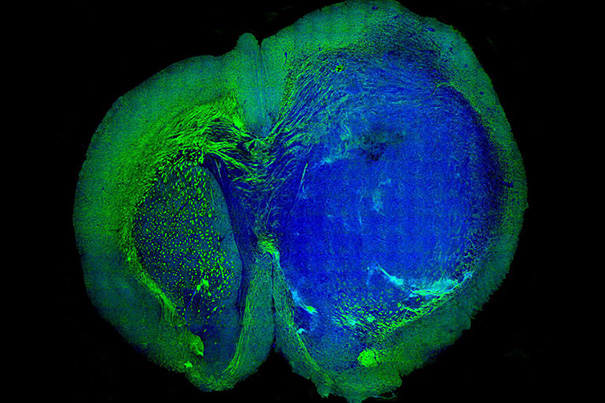

This image of a human glioblastoma brain tumor in the brain of a mouse was made with stimulated Raman scattering, or SRS, microscopy. The technique allows the tumor (blue) to be easily distinguished from normal tissue (green) based on faint signals emitted by tissue with different cellular structures.

Image courtesy of Minbiao Ji, Xie group/Harvard University

Called SRS microscopy — short for stimulated Raman scattering — a team of researchers that included Xiaoliang Sunney Xie, the Mallinckrodt Professor of Chemistry and Chemical Biology, and Minbiao Ji, a postdoctoral fellow in chemistry and chemical biology, were able to “see” the tiniest areas of tumor cells in brain tissue, and to distinguish tumor from healthy tissue in the brains of living mice. Then they showed that the same was possible in tissue removed from a patient with glioblastoma multiforme, one of the most deadly brain tumors. The research is described in a Sept. 4 paper in Science Translational Medicine.

Developed by Xie and colleagues in 2008, SRS works by shining non-invasive lasers into tissue and detecting the weak signal that emerges. By analyzing the signal’s spectrum, researchers can build images of the cellular makeup of the tissue. By amplifying those signals, they transform a technique that once took hours or days into one that works in real time, and could offer a critical insight to surgeons in the operating room.

Since brain tissue and tumors contain different chemical makeups, researchers can create images that precisely show where the tumor “margin” — the boundary area where tumor cells infiltrate among normal cells — is located, helping to guide surgeons in the operating room.